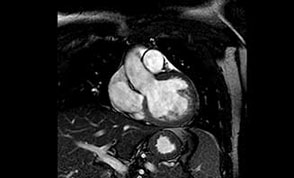

Desde el punto de vista cardiológico, solicitamos un Holter que informó ritmo sinusal con extrasístoles ventriculares y supraventriculares muy poco frecuentes, así como una RMNC con RT que informó una dilatación biauricular, cavidades ventriculares con volúmenes conservados y función sistólica global normal. El grosor de la pared libre era normal. La región apical se encontraba engrosada a expensas de depósito fibroso endomiocárdico. El realce tardío de contraste mostró una gruesa capa de fibrosis subendocárdica que comprometía todo el casquete apical y se extendía a los segmentos medios y basales de las caras inferior, inferolateral, anterolateral y septum posterior (figuras 3 y 4), músculos papilares con fibrosis extensa y válvula mitral con regurgitación grave. La ecografía renal y el Doppler renal fueron normales. Dados estos hallazgos, se completaron los análisis bioquímicos en los que se observó proteinuria de 2g/24 h.

El SAF fue descrito por primera vez en 1983,2 es una entidad autoinmune sistémica poco frecuente y se estima que un 2% de la población general la padece. Se caracteriza por la detección en plasma de anticuerpos antifosfolipídicos, como los anticuerpos anticardiolipina y el anticoagulante lúpico. Clínicamente se manifiesta por episodios recurrentes de trombosis venosa y/o arterial, trombocitopenia, abortos recurrentes y anemia hemolítica autoinmune. Se asocia con alteraciones cardiovasculares, neurológicas, renales y epidérmicas.1,3 El SAF puede ser primario cuando no existe enfermedad subyacente y secundario cuando se asocia con otras patologías, por ejemplo el lupus eritematoso sistémico. Las alteraciones cardiovasculares están presentes con frecuencia y afectan en especial a las válvulas y arterias coronarias,3,4,5 aunque también ha sido informada la presencia de trombos intracavitarios, en particular en pacientes con insuficiencia ventricular derecha.6 La fibrosis endomiocárdica es una miocardiopatía restrictiva que aún hoy tiene una etiología desconocida. Fue descrita por primera por Davies en Uganda en 1948.7Es asociado a múltiples factores etiopatogénicos como raza, clase social, malnutrición, tipo de dieta, infecciones, autoinmunidad, alergia, agentes tóxicos y herencia. Su prevalencia también es desconocida ya que tiene una distribución heterogénea, aunque su mayor localización es en África. Es la miocardiopatía restrictiva más frecuente en el mundo y afecta aproximadamente a 12 millones de personas.8,9 La asociación de SAF con fibrosis endomiocárdica es muy infrecuente. Azeem y colaboradores describieron el caso de un paciente de 50 años con fibrosis endomiocárdica con IC derecha asociada a SAF.10 Gonçalves y colaboradores informaron de un caso de trombosis biventricular en un paciente con fibrosis endomiocárdica con SAF asociado a lupus eritematoso sistémico.11 Con relación a nuestro paciente, debemos decir que al principio pensamos en una miocardiopatía hipertrófica debido a las ondas T negativas del electrocardiograma, la que luego se descartó ya que el ecocardiograma Doppler fue compatible con una miocardiopatía de tipo restrictivo debido a la dilatación biauricular con diámetros ventriculares normales, un patrón de relajación prolongada y el aumento de la ecogenicidad del endocardio, lo que sugería una fibrosis endomiocárdica que luego se confirmó con la RMNC con RT. Las imágenes de RMNC con RT se recomiendan para evaluar la estructura y la función cardíacas, medir la fracción de eyección del ventrículo izquierdo y caracterizar el tejido cardíaco, en especial en sujetos con imágenes ecocardiográficas inadecuadas, cuando no son concluyentes o cuando estén incompletos según lo recomienda la Sociedad Europea de Cardiología con una indicación clase IC.12 Es una técnica no invasiva que además de ofrecer la información anatómica y funcional que otorga la ecocardiografía aporta información adicional, así se considera a la RMNC con RT el estándar en precisión y reproducibilidad de volúmenes, masa y movimiento de la pared. Dado que la RMC ofrece una imagen de buena calidad en la mayoría de los pacientes, es la mejor alternativa para pacientes con estudios ecocardiográficos no diagnósticos. La RMNC con RT es especialmente útil a la hora de identificar trastornos inflamatorios e infiltrativos y para predecir el pronóstico en pacientes con estas enfermedades.13,14 Por otro lado, en nuestro paciente llamaba la atención la negativa de este con respecto a sus antecedentes de hipertensión arterial, pero al permanecer hipertenso durante la internación intentamos buscar otras causas del deterioro renal con proteinuria, que sumado a las lesiones neurológicas, cardíacas, a la trombocitopenia y a la detección del anticoagulante lúpico y de títulos elevados de anticuerpos anticardiolipinas permitió llegar al diagnostico de SAF primario, ya que el paciente no presentaba ninguna asociación con otra patología que justificase un SAF secundario. Las manifestaciones renales del SAF primario pueden ser agudas o crónicas y estar acompañadas de hipertensión e insuficiencia renal progresiva. La proteinuria en rango nefrótico es una infrecuente forma de presentación del SAF primario.15,16 Finalmente, si bien la ecocardiografía nos orientó en el diagnóstico fibrosis endomiocárdica, fue la RMNC con RT el estudio que perfeccionó el diagnóstico presuntivo ya que el realce tardío permitió detectar y delimitar la fibrosis subendocárdica, lo que ha sido informado previamente en algunos reportes y presenta una buena correlación histopatológica en pacientes con fibrosis endomiocárdica.17,18 Consideramos que la asociación de fibrosis endomiocárdica y SAF primario con proteinuria en rango nefrótico es extremadamente infrecuente, lo que coincide con lo encontrado en la literatura y en nuestro caso se expresó en un cuadro clínico muy complejo caracterizado por el compromiso simultáneo neurológico, cardiológico y renal.